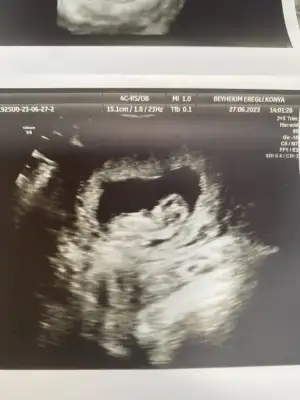

Merhaba 11 haftalık hamileyim bende bir aksilik olmazsa Aralık sonu ile 13 Ocak'a kadar doğum bekliyorum :) Biz cinsiyetini hala sormadık ve öğrenmedik bir süre daha öğrenmeyi düşünmüyorum, eskiden hep kız çocuk isterdim ama nedense oğlum olduğunu hissediyorum,